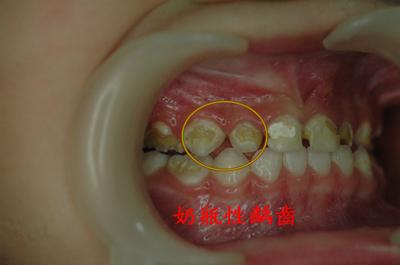

奶瓶龋:一般由婴儿睡眠时不断吸吮奶瓶而造成的龋齿,医学上称为奶瓶龋(又称哺乳龋)。